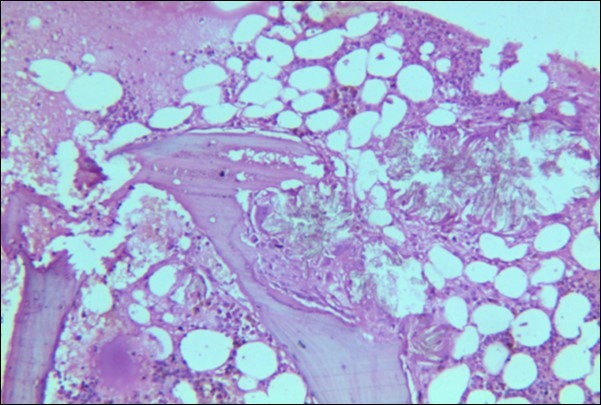

A 30 years old male, resident of Lahore was admitted for opinion regarding the necessity for regular hemodialysis after rejection of second renal transplant. Family history was suggestive of hereditary disease as two of his sisters had died of nephrocalcinosis leading to chronic renal failure at the age of 4 years. Consanguineous marriages in past many generations were also reported. Three cousins of the patient had recurrent stones with normal kidney functions. His past history revealed retention of urine at the age of 5 years due to stone in urethra. Patient presented again after 20 years in 2008 with retention of urine which was relieved by catheterization. Renal ultrasound and X ray KUB reported normal kidneys in both instances. Work up for stone formation was not undertaken at that time. The patient was put on hemodialysis and was planned for transplant which was undertaken in May 2009. After one month, follow up tests revealed Serum Creatinine to be 2.0 mg/dL. Renal Biopsy done in Sep 2009 revealed rejection of transplant. Hemodialysis was started and a second transplant was contemplated. Hemodialysis continued for 2 years till Dec 2011 when second transplant was carried out. A repeat renal biopsy was indicated for increasing serum creatinine. Again transplant rejection was evident on histology. Further investigations revealed Urinary oxalate excretion exceeding 40 mg/day (30 mg Oxalate/gram creatinine). His Blood investigations at the time bone marrow studies revealed bicytopenia with a Haemoglobin of 7.8g/dl, White blood cell count of 5.8 x 109/l; Platelet count of 120 x 109/l. Serum Creatinine was 3.6mg/dl. An attempt to correct the cytopenias by iron, vitamin B12 and folic acid supplements met with failure. No response to anemia could be elicited by adding erythropoietin to the treatment regimen. Renal and bone marrow biopsy were undertaken. Renal biopsy of the patient revealed crystals of calcium oxalate in the tubules (Figure 1). The same crystals were also visualized in bone marrow aspirate (Figure 2a and Figure 2b) and trephine biopsy (Figure 3).

Figure 3.Photomicrograph of bone marrow core from case 1 showing radially arranged calcium oxalate crystals replacing haemopoietic tissue with invasion and destruction of bony trabeculae. Areas of necrosis and a cluster of hemosiderin laden macrophages is visible.

Systemic oxalosis can be a primary or a secondary disease. Primary hyperoxaluria Type 1 (PH 1) is due to the deficiency of glyoxylate aminotransferase and Type II due to that of glyoxylate reductase/D-glycerate dehydrogenase. PH 1 is an autosomal recessive disorder characterized by hyperoxaluria, calcium oxalate urinary lithiasis in childhood, nephrocalcinosis and renal failure which in turn leads to high blood oxalate levels and precipitation occurs throughout the body in the skin, blood vessels and joints. Secondary oxalosis occurs due to oxalate-rich diet, increased absorption or production of oxalate and reduced excretion as seen in renal failure. Variable degree of cytopenias or pancytopenia may accompany extensive oxalosis. Bone marrow aspirate may be unsuccessful due to extensive crystal deposition or accompanying fibrosis. Calcium oxalate crystals are well demonstrated on trephine biopsy with associated fibrosis and occasionally granulomas. They have a grey-yellow radial arrangement on hematoxylin and eosin staining and are birefringent under polarized light.4 Liver biopsy is the confirmatory test which demonstrate reduced glyoxylate aminotransferase activity (PH1). Molecular diagnosis, being non-invasive, is preferred, if available.5 An early diagnosis of oxalosis is of immense value, because at a stage when renal failure has not set in, proper management can arrest or at least delay the progress of disease. However, in patients who have already developed renal failure at the time of diagnosis, a combined liver and kidney transplantation offers the only salvation.6

Both the cases we report here showed prominent bone marrow infiltration by these crystals. Crystals were found imbedded in the bone marrow fragments. Occasional giant cell formation was also seen, however, granulomas were not visualised. The blood cytopenias/ anaemia were suggestive of the underlying pathology. Therefore we suggest that the diagnosis of primary hyperoxalurea be kept in mind when patients present with cytopenia and renal failure at an early age.